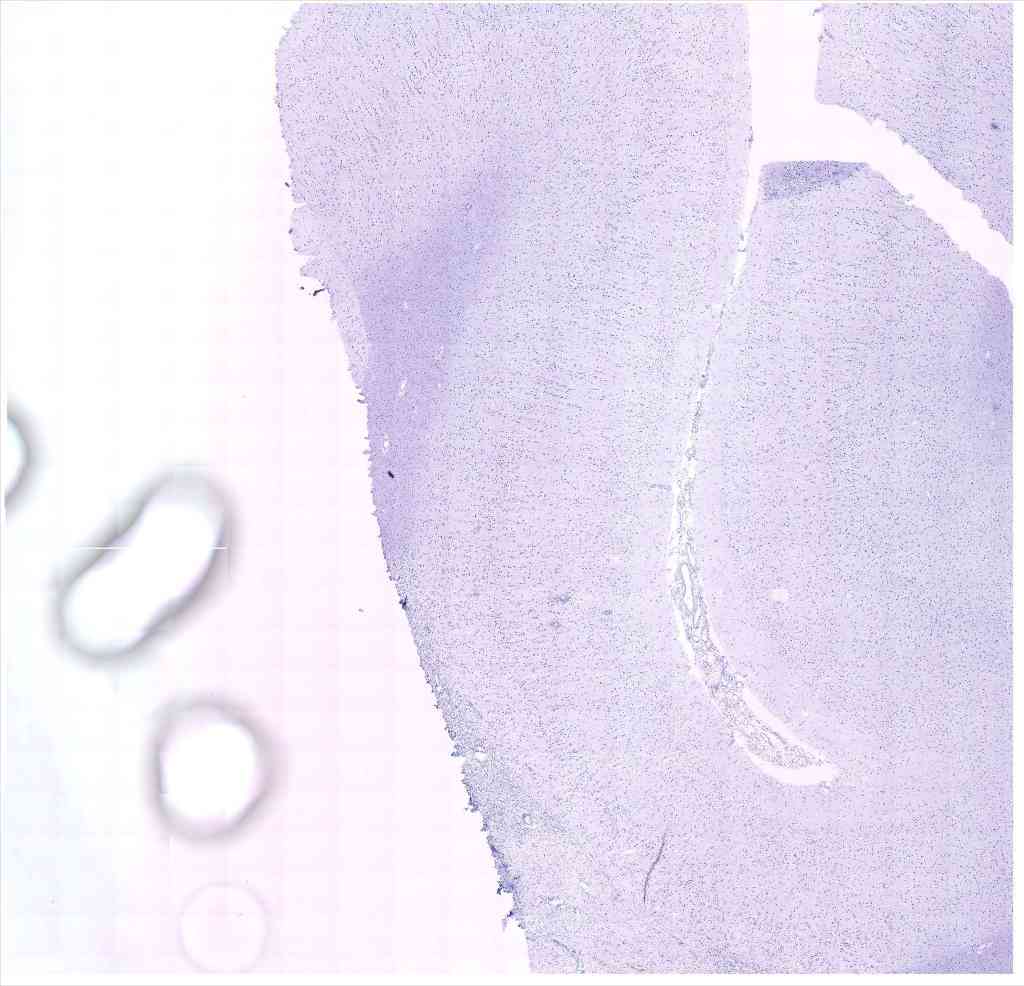

Chip 047 Well D1